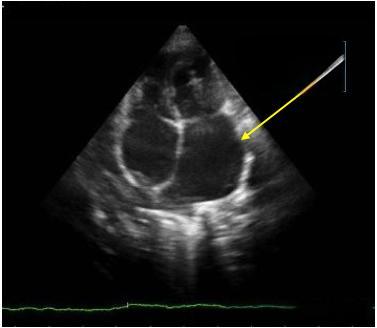

心脏彩超报告中的“左房增大”是一个令人担忧的医学术语。它指的是心脏的左心房腔室体积超出正常范围,这一现象在35岁以上中国乡村居民中的检出率高达6.43%。那么,左房增大究竟是怎么回事?它与我们的日常生活又有何关联?